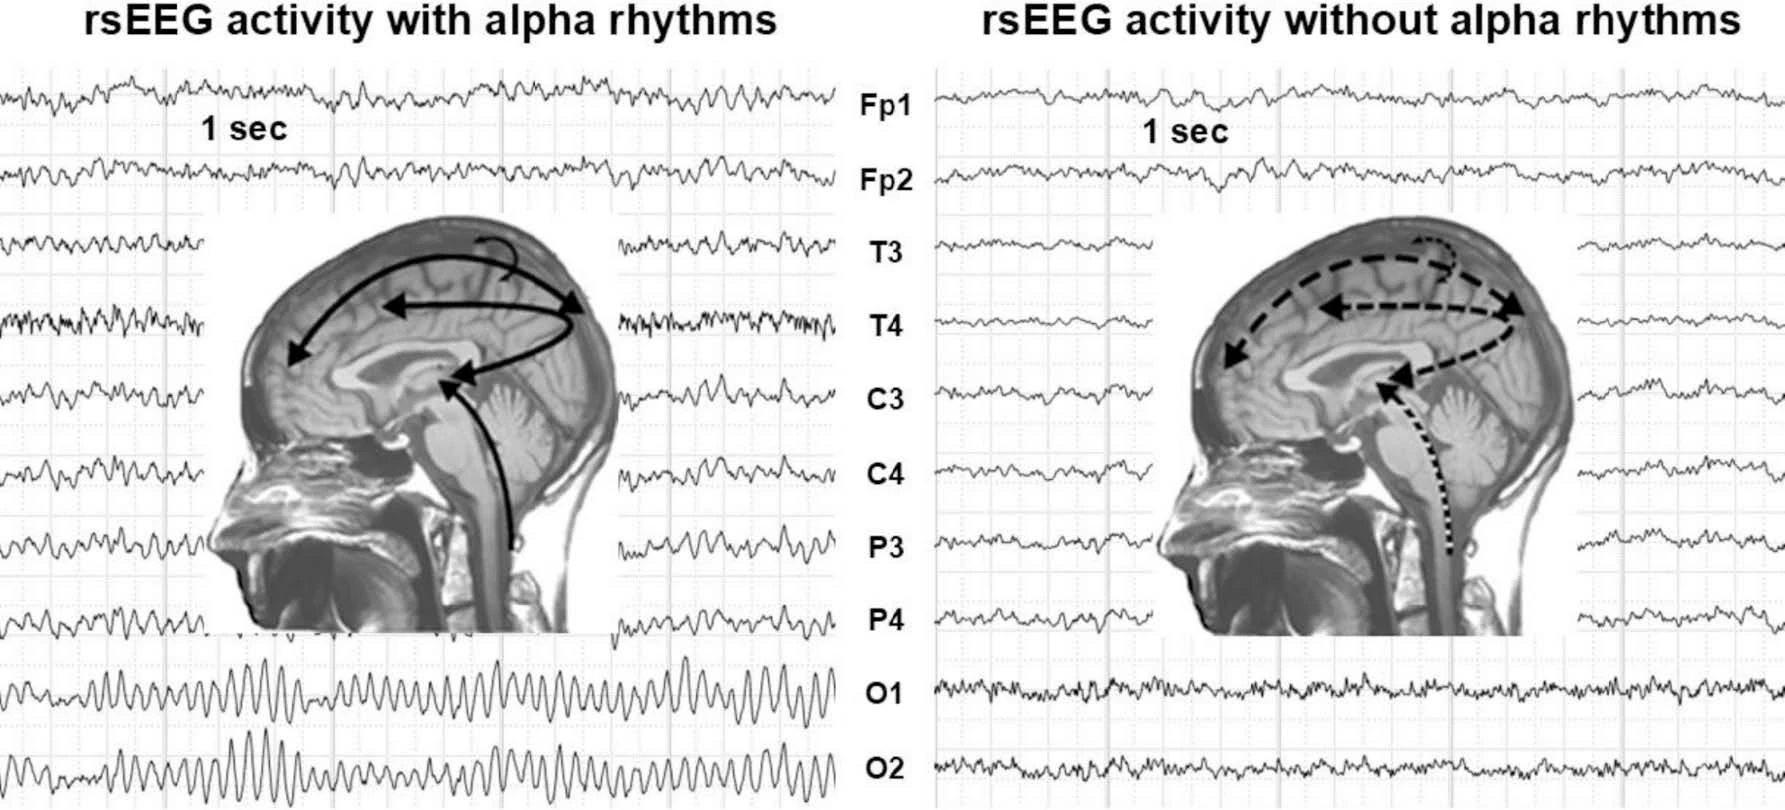

Analisi EEG nei Pazienti con Alzheimer: Esperienze Cliniche e Nuove Prospettive di Monitoraggio Neurofisiologico

Lo studio evidenzia come l’EEG possa identificare alterazioni dei ritmi cerebrali nei pazienti con Alzheimer, correlando la riduzione delle onde alfa con il declino cognitivo e suggerendo il suo impiego come biomarcatore di monitoraggio funzionale.

Le Vene Intra- ed Extracraniche in Relazione con l’Emicrania Cronica: Modificazioni Elettroencefalografiche Indotte dalla Venoplastica con Palloncino

Nei pazienti con emicrania cronica e insufficienza venosa cerebrospinale, la venoplastica con palloncino ha migliorato il flusso giugulare e normalizzato il ritmo alfa cerebrale, con riduzione significativa del dolore e possibile correlazione tra circolazione venosa e attività cerebrale.